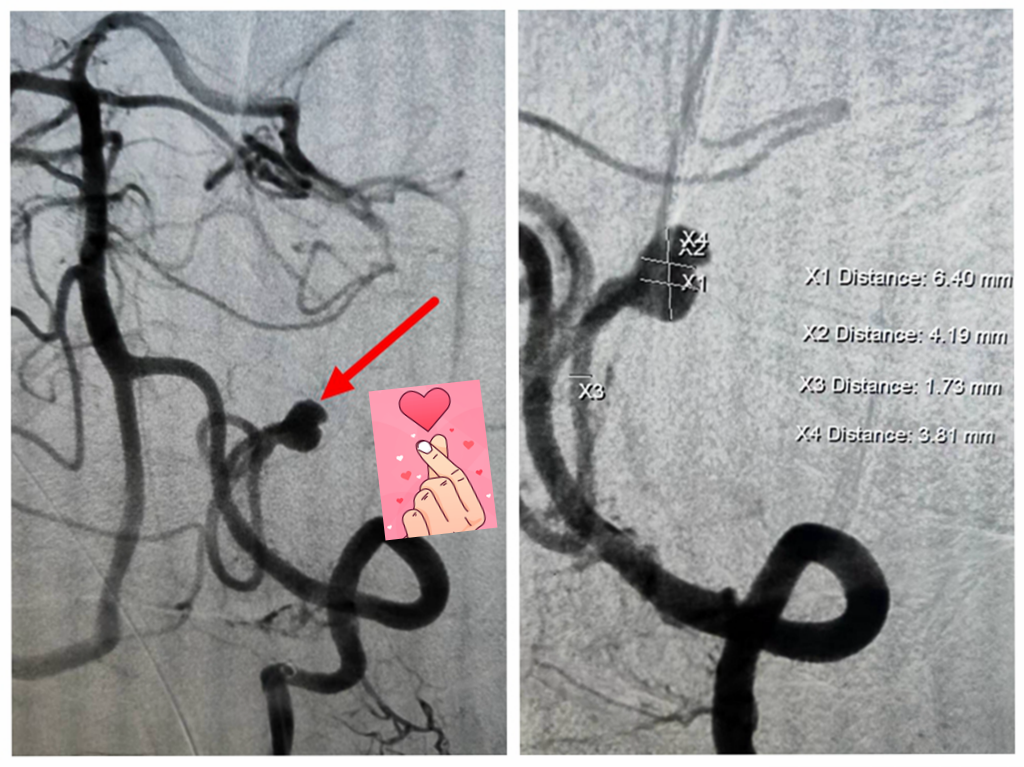

2023-05-16【医疗技术】神内卒中团队开通基底动脉1例

4月26日,10:47分:59岁男性王某,以“意识障碍40分钟”入我院,专科查体可见患者呈昏睡状态,反应迟钝,吐字不清,双眼向右凝视,四肢肌力5-级,NIHSS评分7分。 卒中... -